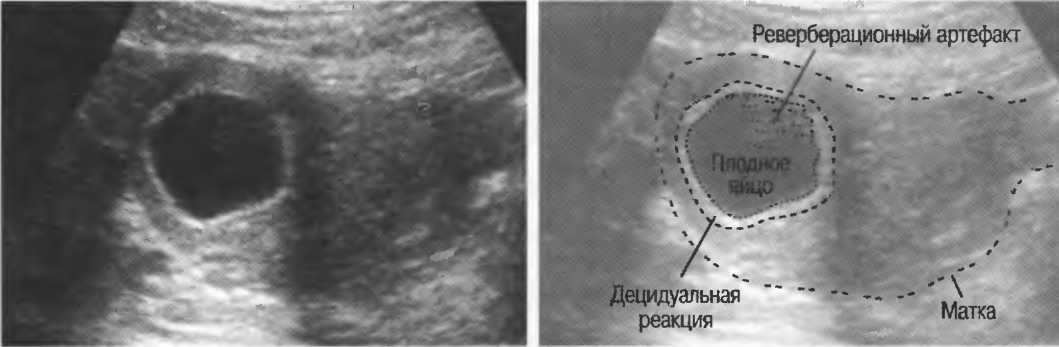

Рис. 15б. Плодные яйца при анэмбрионии: две жидкостьсодержащие структуры с задним усилением и латеральными тенями.

Реверберации

Реверберации имеют место при прохождении ультразвукового луча от одного вида ткани к другому при резко выраженном различии акустического сопротивления этих тканей, например от кишечного газа к печени или ребрам: реверберации могут экранировать ткани, лежащие за газом (рис. 20а).

Реверберации могут полностью менять изображение, создавая линейные структуры или зеркальное отображение. Например, реверберации между параллельными слоями подкожных тканей создают параллельные линейные структуры в мочевом пузыре (рис. 20в).